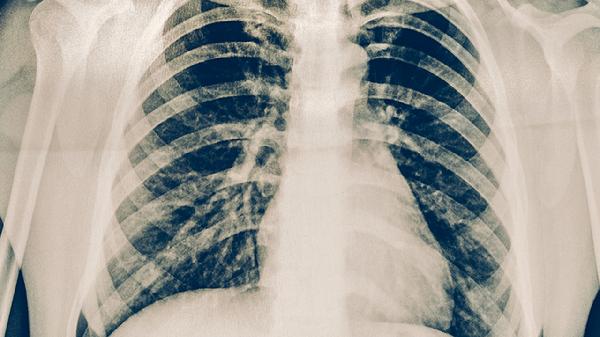

低剂量螺旋CT是目前筛查早期肺癌最有效的手段,能发现直径小于5毫米的肺结节,辐射量仅为常规CT的六分之一。建议长期吸烟者、有肺癌家族史者、长期接触石棉等致癌物的人群每年进行一次筛查。该检查无须空腹,全程无创,检出早期肺癌的概率超过90%。